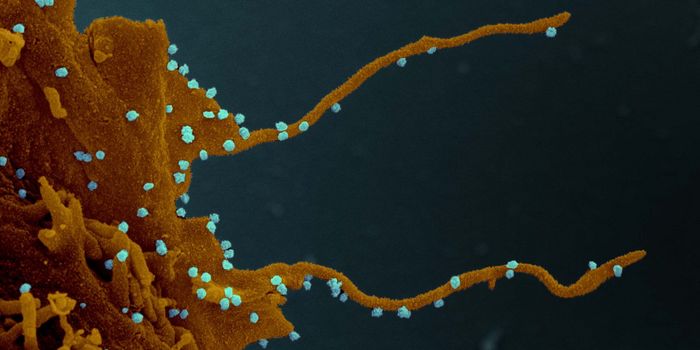

AUG 24, 2020ImmunologyOnce in the body, HIV tracks down T cells that bear the CD4 receptor. It attaches to these immune cells, fusing itself w ...

MAY 23, 2024MicrobiologyWhen human immunodeficiency virus (HIV) emerged and was identified as the cause of acquired immunodeficiency syndrome (A ...

JUL 10, 2020Drug Discovery & DevelopmentPharmaceutical company ViiV Healthcare has announced that its long-lasting, injectable drug, cabotegravir, is more effec ...